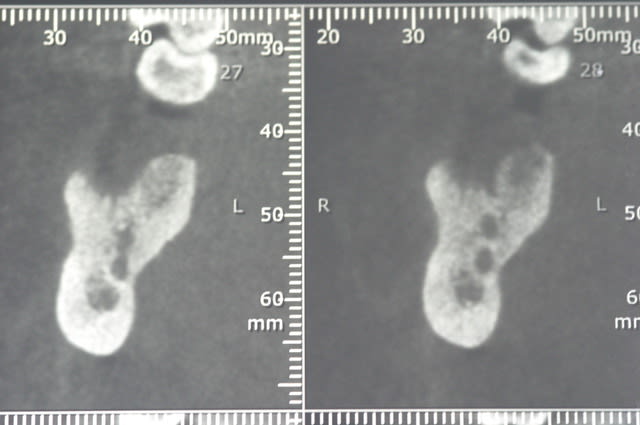

ci joint les photos des coupes scanner d'un patient à qui j'ai proposé de poser un implant afin de remplacer la 36. sur les coupes, on vois nettement le dédoublement du NAI.

tient pour revenir sur ce que disait Pxav, sur une image comme celle ci, vous passeriez en vestibulaire? c'est vrai qu'il y a de la place, mais je n'ai pas osé...